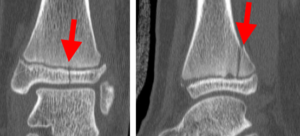

As adolescents approach the end of their growth phase, growth plates begin to close and harden, making them susceptible to transitional fractures during this maturing stage. Two common types of transitional ankle fractures are triplane fractures and Tillaux fractures, which require specific treatment approaches depending on their severity and location (refer to the Treatment section for more details)